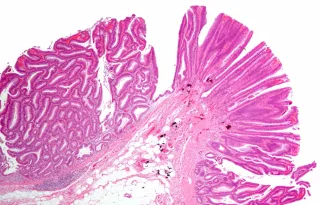

Precancerous colorectal lesions, or dysplasia, in patients with inflammatory bowel disease (IBD) confer markedly different risks of future colorectal cancer depending on dysplasia grade, according to a comprehensive registry study from Karolinska Institutet, Sweden, and NYU Grossman School of Medicine, New York, published in Clinical Gastroenterology and Hepatology.